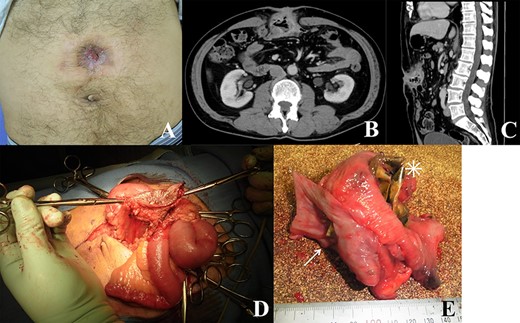

A 61-year-old man underwent abdominal incisional hernia repair using an expanded polytetrafluoroethylene (ePTFE) mesh 5 years back. The patient was referred to our hospital due to drainage from the reddish wound in the abdomen (Fig. 1A). Based on the surgical record, the size of the wound along the previous surgical scar was 8 cm, and the mesh was placed in the abdominal cavity using the Ventrio mesh (Bard, Warwick, Rhode Island, USA) (8 × 12 cm) and was fixed with four stitches. Laboratory test revealed a slightly elevated C-reactive protein level at 0.83 mg/dL. The symptoms were believed to be caused by mesh infection, mesh removal surgery was planned to control infection. Contrast-enhanced abdominal computed tomography (CT) scan revealed recurrence of abdominal incisional hernia with local intestinal wall thickening (Fig. 1B and C). The surgery was performed by cutting along the midline of the operative scar approximately 15 cm, the intraoperative finding was high degree of adhesions in the abdominal cavity. Moreover, the small intestine and transverse colon formed a mass, and the mesh was not visible but palpable (Fig. 1D). Two parts of the small intestine and transverse colon resection were resected, and three anastomoses were created. In terms of the remaining rectus sheath and the site of infection, direct suturing was performed. Based on the examination of the excised specimen, most part of the mesh had penetrated and was exposed in the small intestine, the corners of the hardened and bent mesh penetrated the transverse colon and the other parts the small intestine (Fig. 1E). Postoperative wound infection was observed and it was treated with abscess drainage, the patient was discharged 24 days after the surgery. On histological examination, the mesh penetrated the small intestine and colon, and the small and large intestines were lumped together causing inflammatory fibrous adhesions.

(A) Image of the patient’s abdomen before surgery. Reddish wound and fistula; (B and C) contrast-enhanced CT scan showing recurrence of abdominal incisional hernia with intestinal wall thickening; (D) intraoperative findings; skin, abdominal wall and intestines forming a mass; (E) excised specimen; mesh migrating through the small intestinal wall (asterisk) and its corner penetrating the colon (arrow).